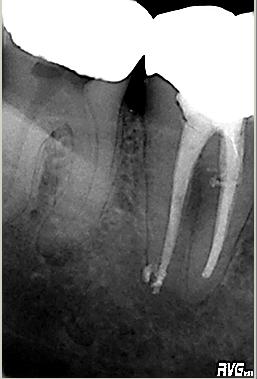

Masterpoinaufnahme

Masterpoinaufnahme. Mesial konnte keine „Patency“, das bewußte offenhalten des foramen apicale, hergestellt werden. Das distale Kanalsystem konnte gängig gemacht werden

WF-Kontrolle

Erste WF-Kontrolle. Das „Down Pack“, der apikale Anteil der thermoplastischen Wurzelfüllung des distalen Kanalsystems wird separat röntgenologisch überprüft